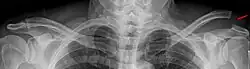

L'épaule (nom féminin) est la région morphologique se situant à la jonction du tronc avec le membre supérieur.

L'épaule comporte 2 articulations qui fonctionnent de concert et qui concourent à en faire le complexe articulaire le plus mobile du corps humain. Elle permet d'orienter le membre supérieur dans l'espace, autorisant en particulier son extrémité effectrice, la main, à assurer ses rôles de préhension et de communication avec l'environnement situé à sa portée.

Le complexe articulaire de l'épaule met en relation quatre os :

- le manubrium sternal (ainsi que le premier cartilage costal) ;

- la clavicule ;

- l'omoplate (scapula) ;

- la tête humérale.